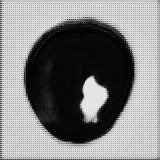

Main Module . The main module aims to generate two selective cuts, which separate the normal and abnormal information in an input image. The follows an encoder-decoder architecture like the U-Net, including one encoder and two decoders. The encoder extracts features of an input image , which could be an image located within or outside of the reference distribution , a collection of normal images. One decoder, the second upsampling branch, is designed to generate a “fence” cut that is constrained by an image fence formed by . The aims to generate an image and tries to fool the discriminator . The other decoder, the first unsampling branch, is designed to generate another “wild” cut , which captures leftover image content that is not included in . As a result, the produces another images to complement the fence-cut output . Since the wile-cut output is complementary to the fence-cut output, image information that can not be covered by the reference distribution would be included in the while-cut output, like the anomaly. The complementary relation between these two cuts and is enforced by a positive Dice loss, i.e., a “disjoincy” loss as discussed in the paragraph of Loss Functions. Figure 2 demonstrates the “disjoincy” of and , like their complementary histogram distribution and different thresholded images at different peaks.

Except for a weak guidance of the “disjoincy” loss for the “wild” cut, we adopt a reconstruction branch to make sure our two selective cuts include enough information to constrcut a coarse version of the original input. The reconstructor consists of a convolution layer with the Sigmoid as the activation function, which is applied on the concatenation of the two-cut outputs and to regenerate the input image back. This reconstructor ensures that the does not generate an image far from the input image and also ensures that the does not generate an empty image if the anomaly or novelty exists. Figure 3 shows the histogram separation of the reconstructed images, compared to the original input images which present complex histogram peaks and have difficulty in separating the brain tumor from backgorund and other tissues via a simple thresholding. The discontinuous histogram distribution of is inherited from the two generated sub-images and through a simple weighted combination. As a result, the segmentation task becomes relatively easy to be done on the reconstructed image .